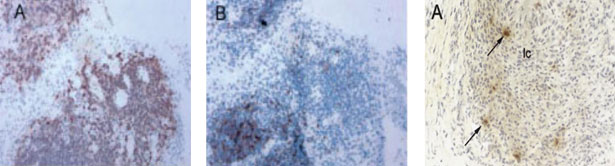

На рис. 5 представлены лимфоплазмоцитарные инфильтраты при ревматоидном синовите, принимающие формы фолликулоподобных структур и иммуногистохимическую идентификацию хемокина CXCL13 в этих структурах в синовиальной оболочке при РА в крайнем справа фото.

Рис. 5. Слева (А, В) видны лимфоплазмоцитарные инфильтраты при ревматоидном синовите, принимающие формы фолликулоподобныхструктур (Х 100), по материалам [160] Крайний справа снимок отражает иммуногистохимическую идентификацию хемокина CXCL13 (указано стрелками) в фолликулоподобной структуре в синовиальной оболочке при РА (Х 100), по материалам [68]